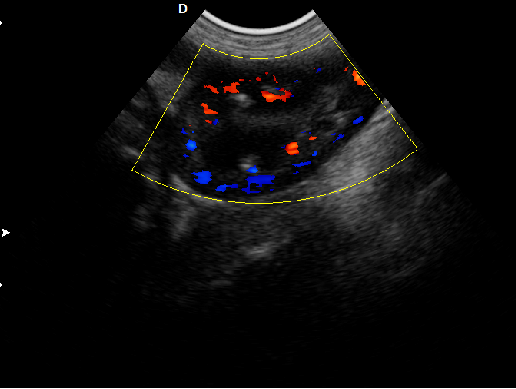

P5-VET手提式獸用彩超機(jī)心臟超聲檢查圖

心臟超聲檢查:

心臟超聲是唯一能動(dòng)態(tài)顯示心腔內(nèi)結(jié)構(gòu)、心臟的搏動(dòng)和血液流動(dòng)的儀器,對(duì)人體沒(méi)有任何損傷。心臟的各個(gè)結(jié)構(gòu)清晰地顯示在屏幕上。通過(guò)彩超的測(cè)量,醫(yī)生可了解瓣膜病變的程度以決定保守治療還是手術(shù)治療。心肌的增厚、心腔的擴(kuò)大都要依賴彩超來(lái)判斷;對(duì)冠心病,彩超能直觀顯示心肌的運(yùn)動(dòng)狀況及心功能,向臨床醫(yī)生提示心肌缺血的部位。